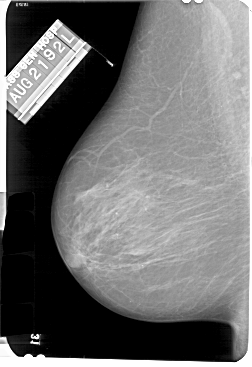

A_1131_1.LEFT_CC

LEFT_CC LINES 5491 PIXELS_PER_LINE 3586 BITS_PER_PIXEL 12 RESOLUTION 43.5 NON_OVERLAY